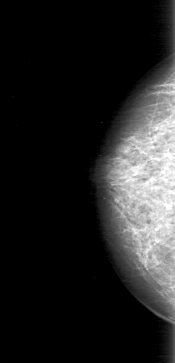

D_4038_1.LEFT_MLO

RIGHT_CC LINES 5071 PIXELS_PER_LINE 2446 BITS_PER_PIXEL 12 RESOLUTION 43.5 NON_OVERLAY

RIGHT_MLO LINES 5266 PIXELS_PER_LINE 2326 BITS_PER_PIXEL 12 RESOLUTION 43.5 NON_OVERLAY